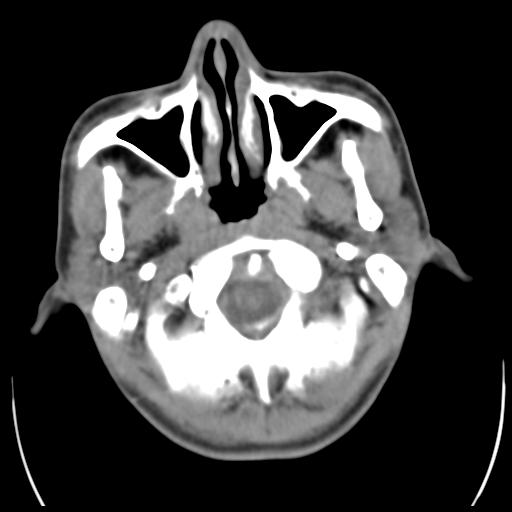

35m 鼻子时不时流血,头及右侧面部痛,颈部淋巴结未见明显大

这个东西大家仔细看看呀

蝶窦,后组筛窦及鼻咽部团块状软组织影,骨壁破坏,病变较广泛。考虑恶性肉芽肿。建议活检。

考虑中线肉芽肿(鼻硬结病),次之tb或真菌感染性肉芽肿,病变形态不像肿瘤,建议增强及活检。

蝶窦,后组筛窦及鼻咽部团块状软组织影,骨壁破坏,病变较广泛。考虑炎性肉芽肿性病变可能。建议活检。